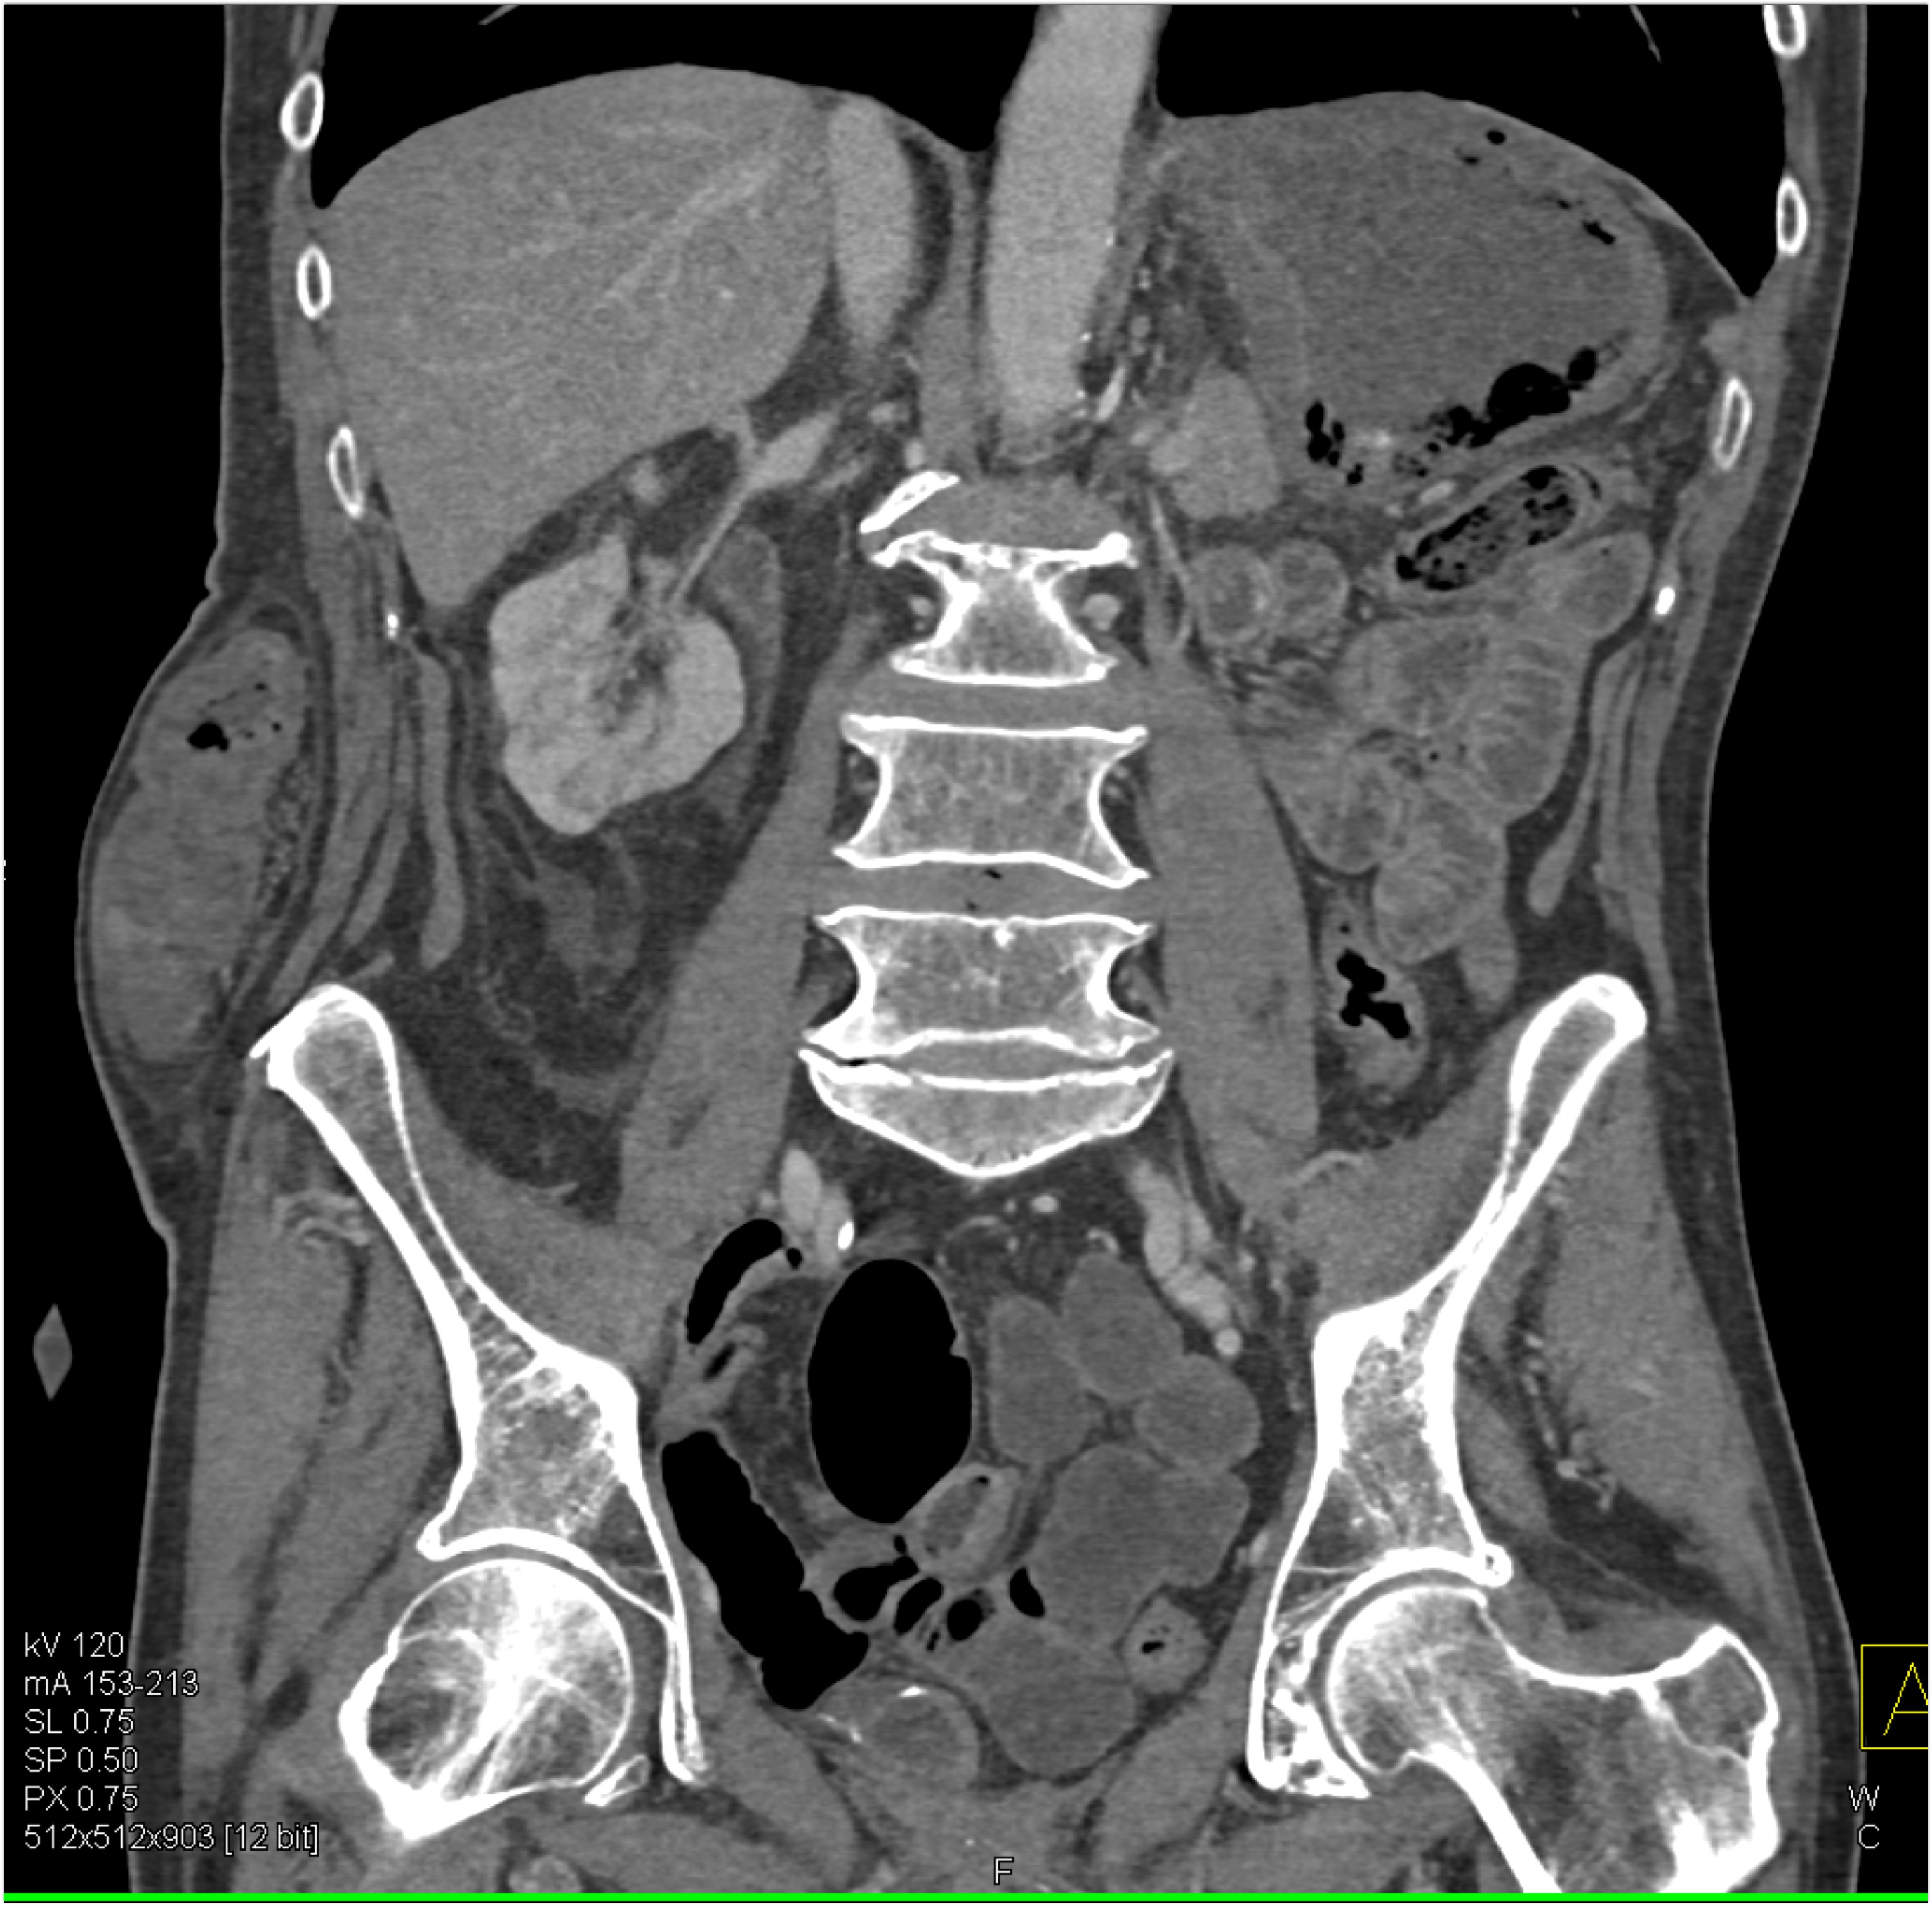

7) In this patient with pelvic pain the best diagnosis is?

lymphoma

silicon injection into buttocks

neurofibromatosis

intramuscular hemorrhage